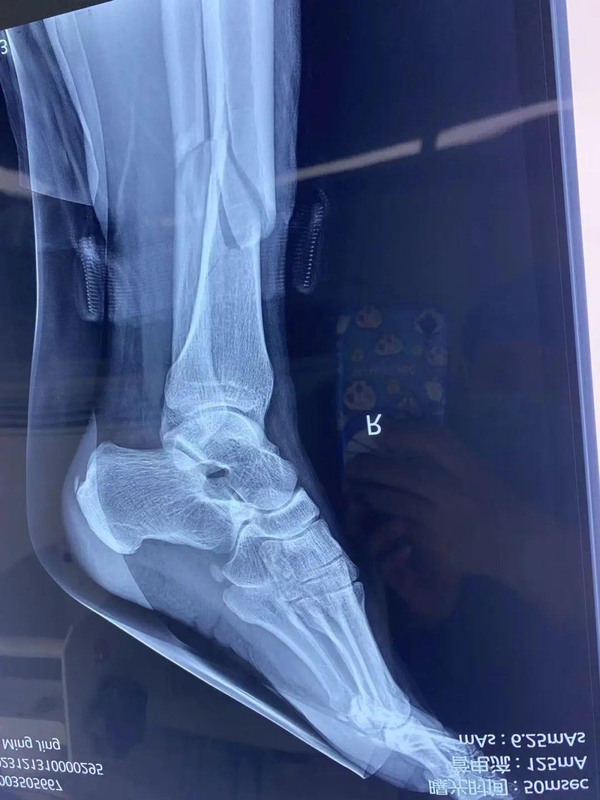

【胫腓骨骨折 】

【基本资料】患者:女,36岁

本病例胫骨骨折。

【术前X片】